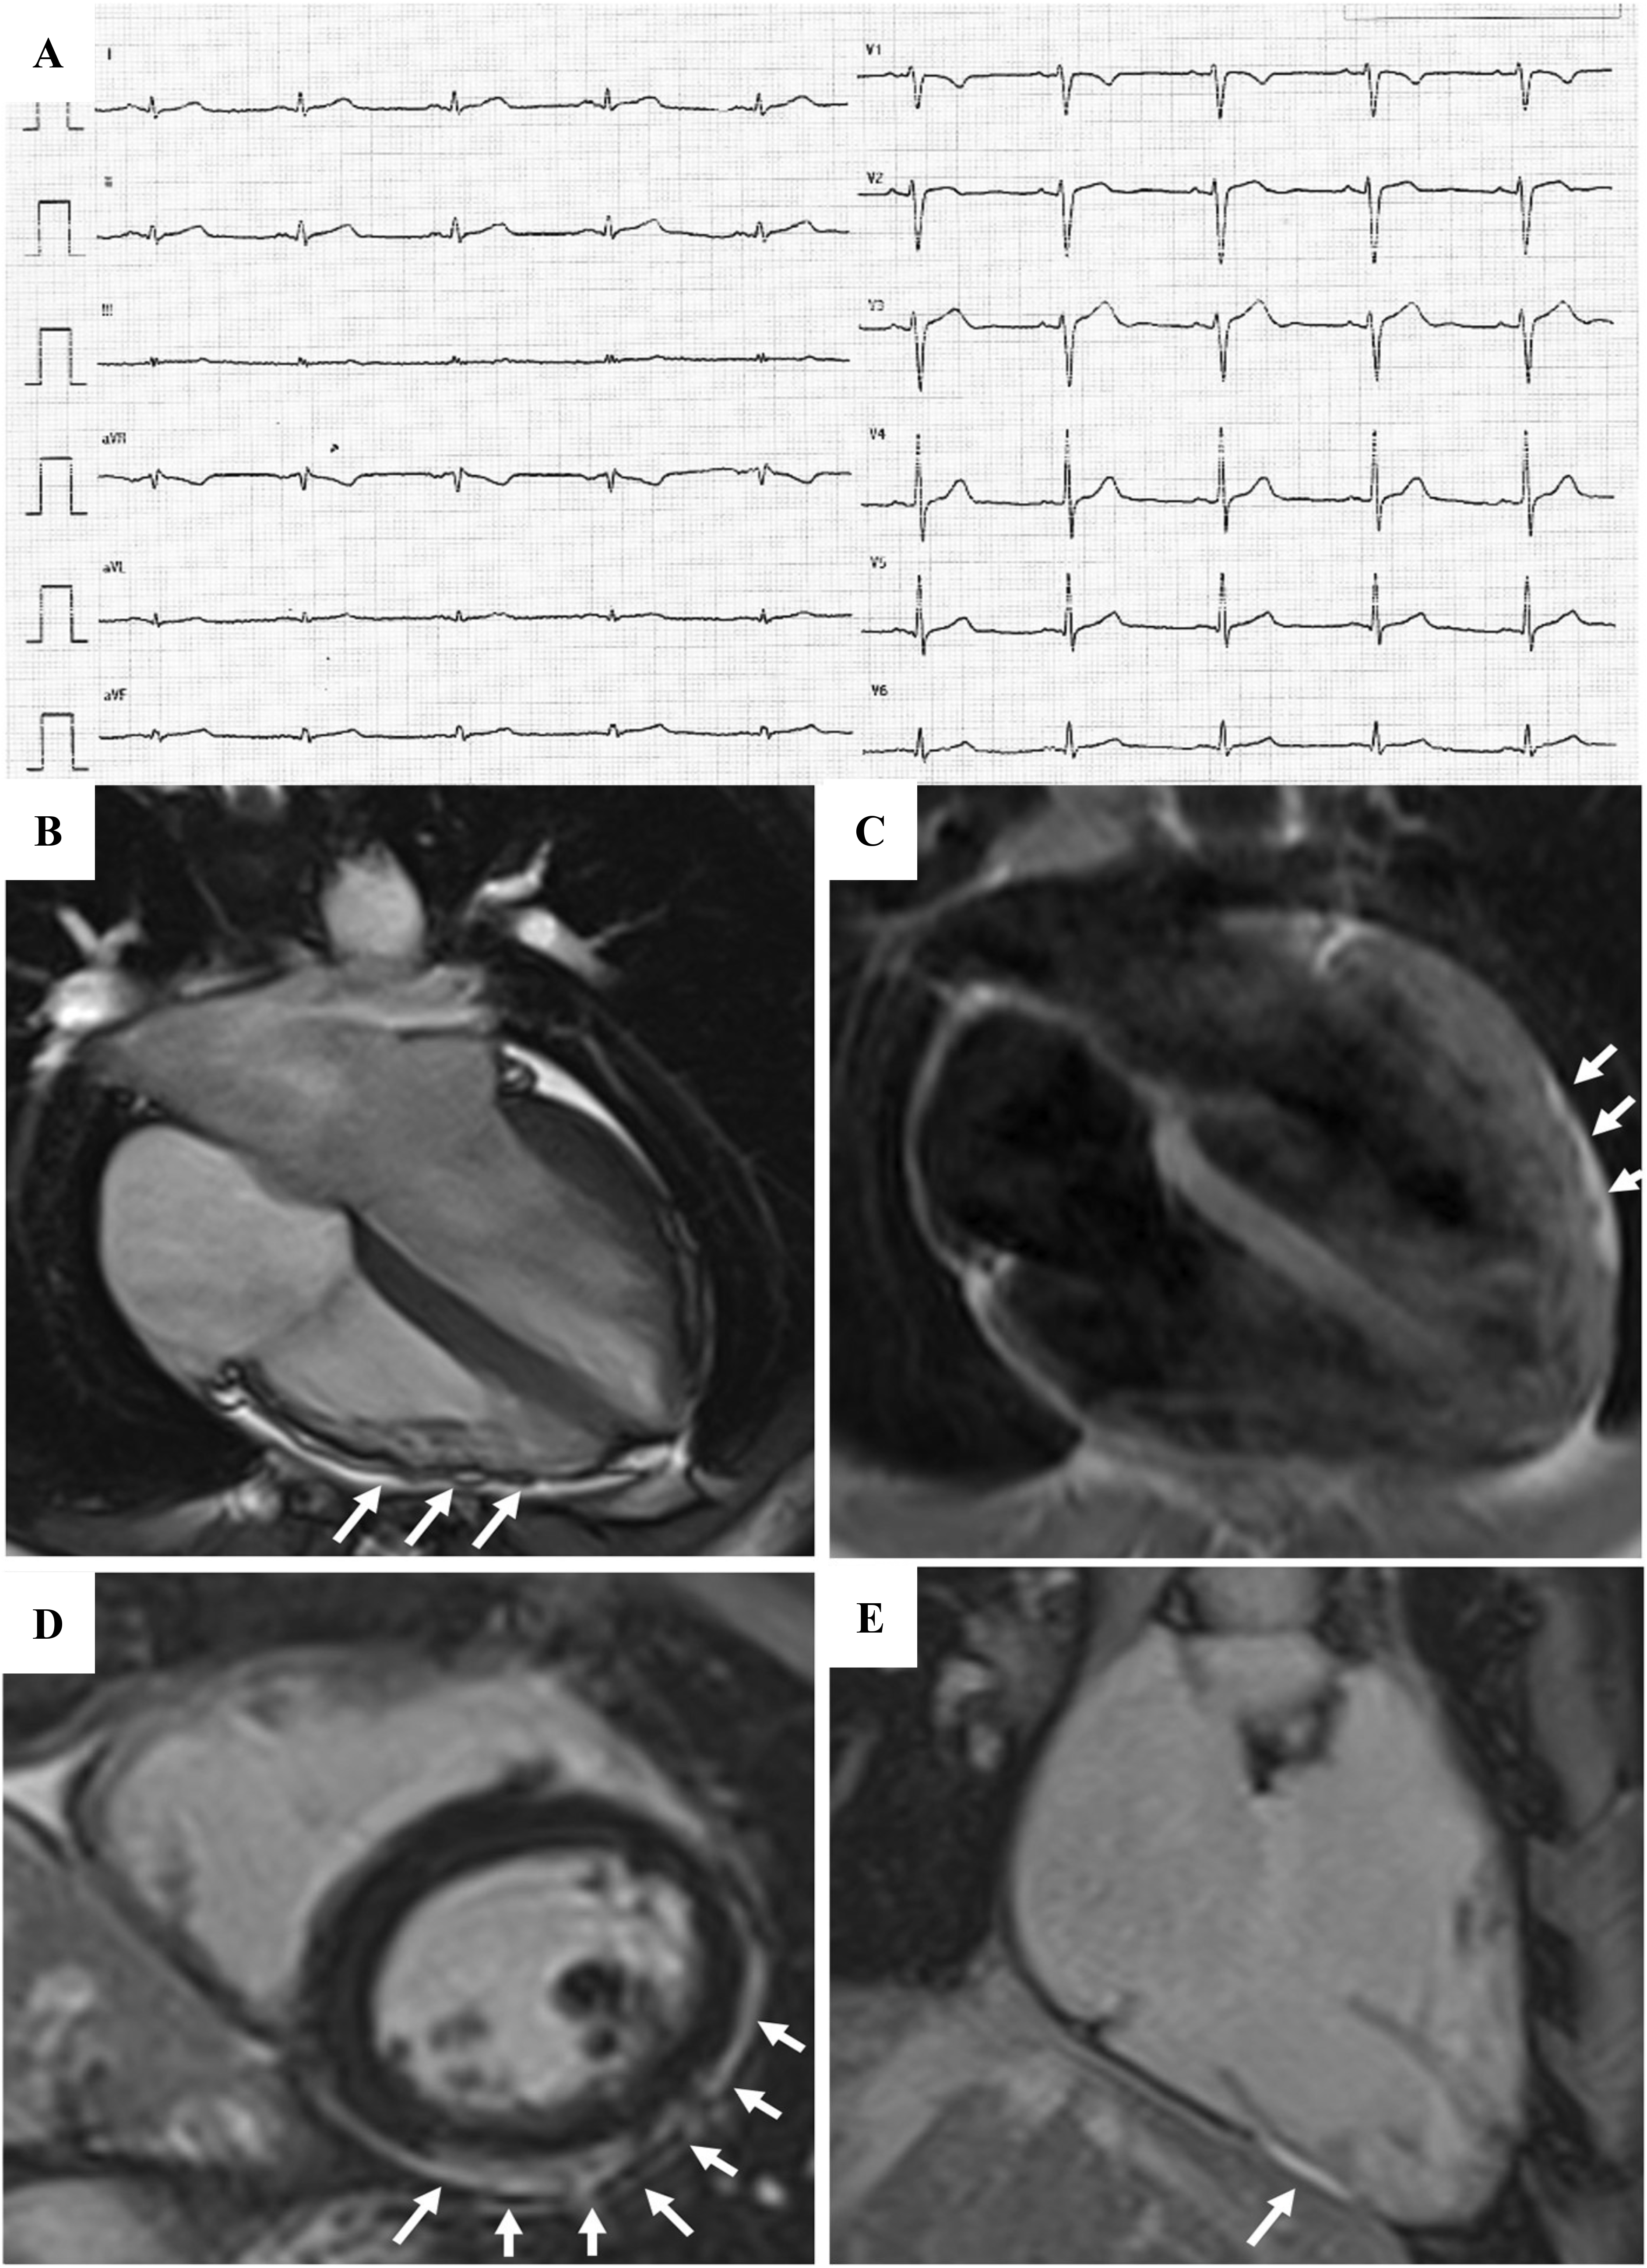

The introduction of non-invasive tissue characterization with CMR is one of the most important innovations of the 2020 criteria. The major CMR criterion is the presence of transmural LGE in at least 1 RV segment, confirmed in 2 orthogonal views. Currently, the diagnostic specificity of RV LGE is considered high, instead the sensitivity is low. This is due to the CMR technology characterized by a poor spectral resolution and suboptimal contrast/noise ratio in quantifying the thin RV wall [17, 28, 29, 30]. The highest specificity is reached when wall motion abnormalities and pre/post contrast signal alterations are considered together [29] (Fig. 3, Ref. [31]).

Fig. 3.Clinical features of ARVC. Basal ECG, exercise testing ECG and CMR findings in a 38-year-old woman hospitalized for sustained VT. Basal ECG showed TWI in V1–V5 and flattened T wave in inferior leads (A). Exercise testing revealed frequent PVBs and a non-sustained VT with LBBB/superior axis morphology, originating from RV free wall (B). CMR revealed mild RV dilatation, moderate RV systolic disfunction, a wide peritricuspid aneurysm, with an extreme thinning of the wall (four-chamber cine view in diastolic phase, C, and systolic phase, D). The PD-TSE sequences revealed fatty infiltration of the RV wall, especially in the subtricuspid region (E, and magnified on the top of F). No RV LGE was identified, not even in the same regions of RV fatty infiltration, maybe because an extreme thinning of the RV wall (F on the bottom). The diagnosis was “definite ARVC”. ARVC, arrhythmogenic right ventricular cardiomyopathy; CMR, cardiac magnetic resonance; LBBB, left bundle branch block; LGE, late gadolinium enhancement; PD-TSE, positron density-turbo spin echo; PVBs, premature ventricular beats; RV, right ventricle; TWI, T wave inversion; VT, ventricular tachycardia. Adapted from Graziano et al. [31].